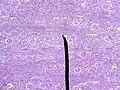

Microscopic cross section of the renal cortex